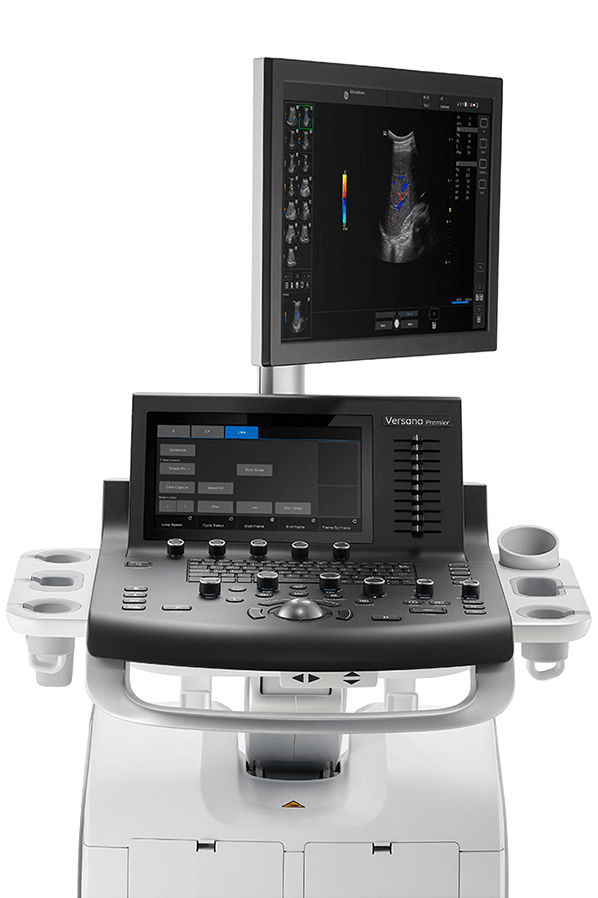

УЗ-сканеры Versana – это оборудование премиум-сегмента, которое подходит для комплексного обследования:

Высококлассная визуализация

Эргономичные опции

Умные приложения

Универсальные датчики